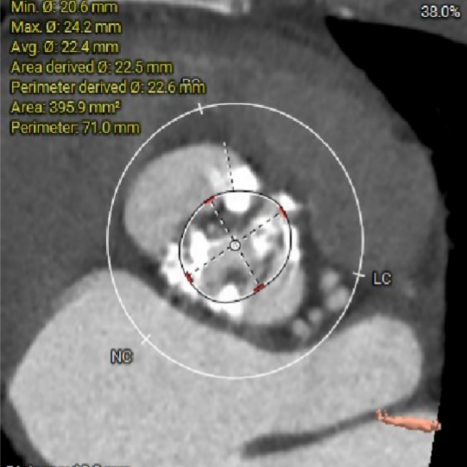

主动脉根部CTA:

根部概览:

ANNULUS